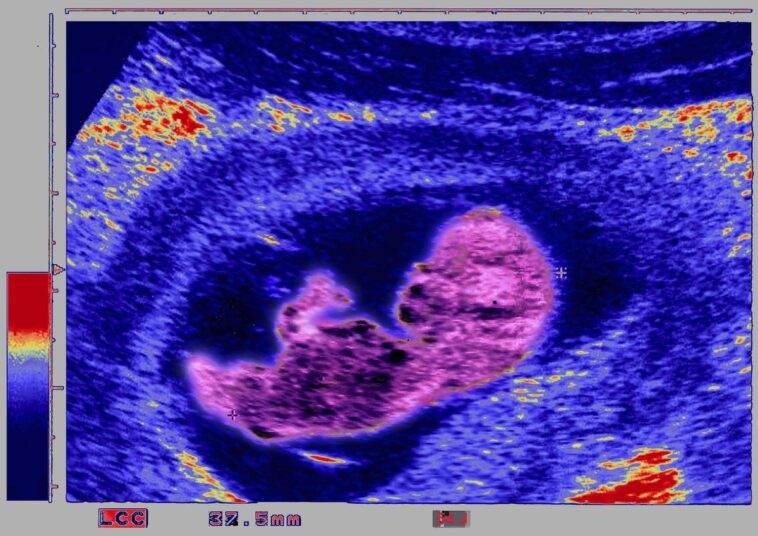

Ultrasound Biometry Of The Fetus, Saggital Section, Fetus In Utero In The Third Month, Measured By … [+]